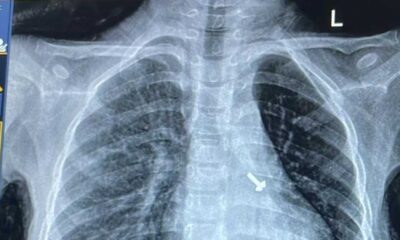

07 वर्ष के बच्चे के फेफड़े में फंसे पेंच को निकालकर एम्स के चिकित्सकों ने दिया जीवनदान

February 18, 2025ऋषिकेश: अखिल भारतीय आयुर्विज्ञान संस्थान, ऋषिकेश के पल्मोनरी मेडिसिन विभाग की ओर से संचालित ब्रोंकोस्कोपी प्रयोगशाला...